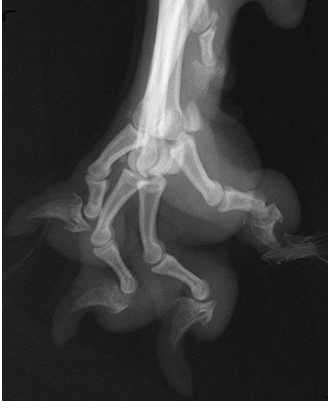

what radiographic view of the digits is shown?

splayed lateral view of the digits